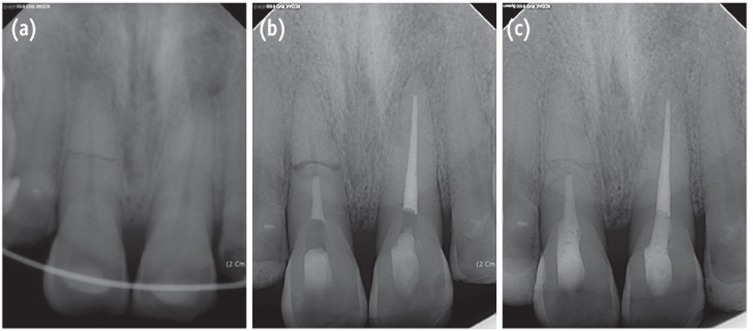

A 60-year-old male patient was referred to the Department of Conservative Dentistry at the Wonkwang University Dental Hospital (Iksan, Korea) for the evaluation of the maxillary anterior teeth. He had a history of trauma that had occurred 7 days previously. The patient's medical history was noncontributory. The initial diagnosis by the emergency dentist was horizontal root fracture on the maxillary right central incisor and avulsion on the maxillary left central incisor. According to the emergency note, a crown fragment of tooth #11 had been extruded with a large amount of diastases. The emergency dentist performed pulp extirpation on the crown fragment and the teeth were repositioned and splinted with a semi-rigid splint (Figure 3a). Root canal treatment was performed on coronal fragment of tooth #11 with K-file and irrigated with 5% sodium hypochlorite. Working length was established with an apex locator (DentaPort ZX). After 6 weeks of intracanal calcium hydroxide dressing, the canal was obturated with MTA (ProRoot) (Figure 3b).

At the 2-year follow-up evaluation, the patient had no complaints of pain or discomfort. Radiographic examination showed the root-fractured tooth was completely healed with hard and soft tissue between the fragments (Figure 3c).

Andreasen and Hjorting-Hansen classified the healing of root-fractured teeth into four groups, (1) healing with hard tissue, (2) healing with the interposition of hard and soft tissue, (3) healing with interposition of soft tissue, and (4) no healing.12 The factors influencing the healing of a root-fractured tooth include the patient's age, stage of root growth, mobility of the coronal fragment, and diastasis of the fragments.1 In the present patients, injury factors (e.g., fragment diastasis and mobility of the coronal fragment) exerted a strong influence on healing at the fracture line and on pulpal necrosis. Case 1 had small diastasis of less than 0.5 mm and no mobility, and the tooth healed with hard tissue and with the evidence of a spontaneous healing process such as ISR. Case 2 showed extrusive luxation of the crown fragment with a large amount of diastases. It was impossible to determine whether the pulp was vital because root canal treatment had been already initiated by the emergency dentist. The follow-up radiographs showed healing with hard and soft tissue. Case 3 showed lateral luxation of the crown fragment with a large amount of diastases. Interposition of soft tissue with pulp necrosis of coronal fragment was also observed. Increasing diastases between fragments reportedly increases the risk of pulp necrosis, and decreases the likelihood of hard tissue healing.13 According to a report, the frequency of pulp necrosis is stable with diastasis of up to 1 mm, whereas hard tissue healing shows stable values up to 0.5 mm.13

Figure 3

Radiograph of the right maxillary central incisor with horizontal root fracture. (a) After repositioning and applying a resin-wire splint; (b) After root canal treatment; (c) At the 2-year follow-up evaluation. 2-year follow-up radiograph reveals healing with the interposition of hard and soft tissue between the fragments.